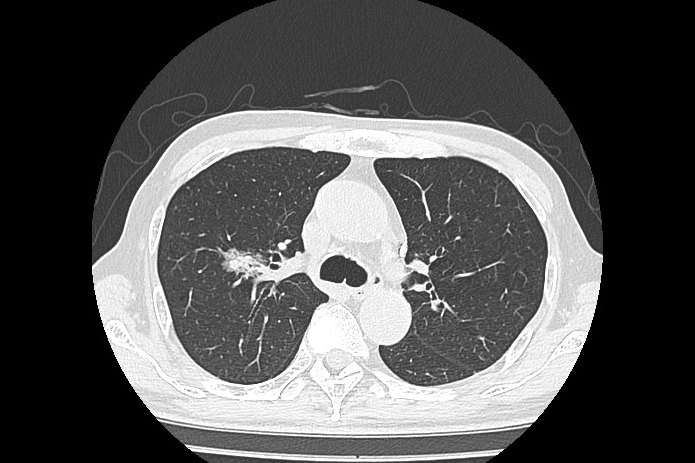

胸部CT

CTはGE社製16列MDCT Brivo CT385を使用しています。CT検査ではX線を人体に照射し、体内を通過したX線量をコンピュータでデータ処理することで画像化しています。一般のX線写真では分からないような微細な体内の情報を得ることができます。また、MRI検査とは異なり短時間で検査することができます。また、最新の被ばく低減技術を搭載することで、低被ばくの検査を実現し、特に被ばく感受性の高い部位である、水晶体・甲状腺・乳腺においても、自動コントロール機能を有することで、最適な検査を実現します。

胸部CTでは、肺がんが心配な方、タバコを吸っている(いた)方、周りの副流煙が気になる方など胸部X線写真で骨に重なって判断しにくい病変が、CTでははっきりと写し出すことができます。